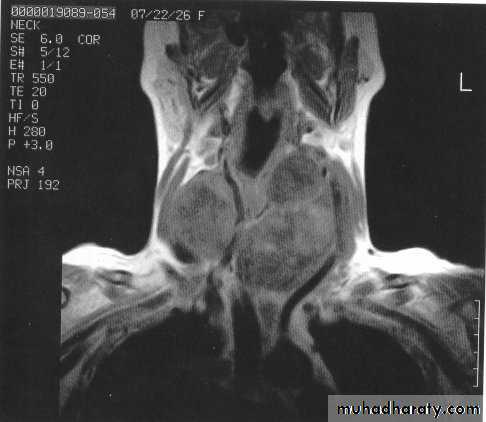

3-CT scan and MRI: assessment of known malignancy, extent of retrosternal and occasionally recurrent

Goitres.